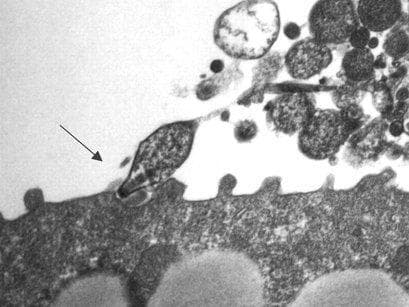

Mycoplasma pneumoniae est une bactérie parasite, le seul mycoplasme dont la pathogénicité pour l'homme soit bien établie. Trouvé dès 1944 par le microbiologiste Monroe Davis Eaton chez des sujets atteints de « pneumonie atypique primitive » ou « pneumonie à virus », il fut longtemps dénommé « agent d'Eaton » et reconnu comme n'étant pas un vrai virus en raison de sa sensibilité aux tétracyclines. C'est en 1962 que Robert M. Chanock réussit à le cultiver sur milieu non vivant et à prouver son appartenance aux mycoplasmes. Le germe se trouve essentiellement dans les voies respiratoires, où il peut provoquer une véritable pneumonie avec hépatisation : entre 30 et 50 % des pneumonies primaires atypiques, les autres étant dues aux adénovirus et aux rickettsies. Il est apparu dans les expériences sur volontaires et lors d'enquêtes épidémiologiques que seule une minorité d'individus développe des lésions pulmonaires (3 à 15 %). Dans la majorité des cas, l'infection est bénigne et se manifeste par un épisode de bronchite aiguë ou de pharyngite, parfois de myringite. Des formes plus aigües ont été rapportées, principalement des bronchiolites aiguës hypoxémiantes et des syndromes de détresse respiratoire aiguë. La maladie touche de préférence les adolescents et les jeunes adultes. L'incubation est longue (jusqu'à 3 semaines) et le portage pharyngé peut se prolonger pendant plusieurs semaines ou plusieurs mois chez le convalescent. La culture des expectorations ou d'un frottis pharyngé est laborieuse et lente. Le germe exige un milieu spécial enrichi d'extrait de levure et de sérum. La primo-infection peut exiger 15 jours et plus. Mycoplasma pneumoniae hémolyse les globules rouges de cobaye, fermente le glucose et réduit le phényl tétrazolium. C'est le procédé le plus souvent employé pour le diagnostic clinique, mais il exige l'examen d'un sérum précoce et d'un autre plus tardif (différence de titres). Il peut se faire par : Déviation du complément. Inhibition de l'hémagglutination. Immunofluorescence indirecte sur coupes d'embryons de poulets infectés.